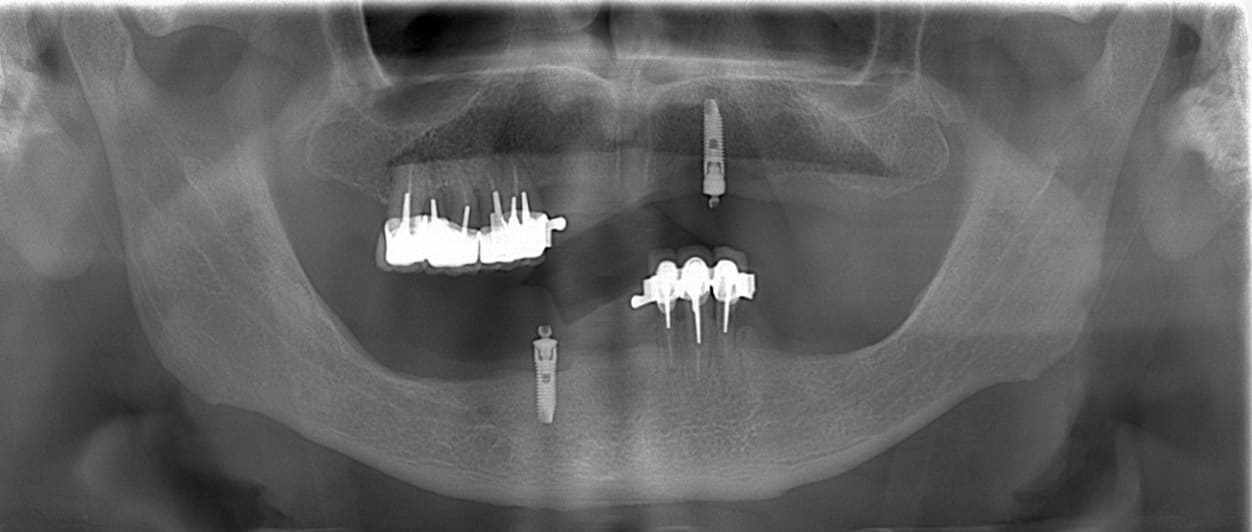

peux-tu, stp, identifier ces 2 implants? ça me fait penser à du dentium, mais l'accastillage ne parle pas dans ce sens.

Je ne peux pas t'aider mais je crois n'avoir jamais vu un nerf alvéolaire inférieur si crestal avec une résorption osseuse limitée

comme d'hab, je vais me répéter....pour une identification il me faut de bonnes rétro montrant l'intégralité des implants du col à l'apex et bien orthogonal pour avoir le max d'informations sur "l'anatomie" de ces implants, merci....

par contre sûr que c'est pas du dentium....là c'est plutôt du 3i ou de l'Anthofit Anthogyr ou similaire....mais pour avoir la réponse...il me faut les rétros...